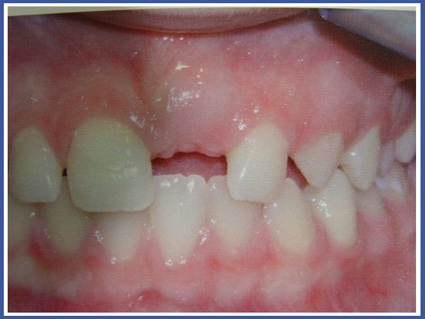

גודר לשון-מהו?

מתקן אורתודונטי המיועד לטיפול במקרים של מנשך קדמי פתוח, בעיקר על רקע מציצת אצבע או מוצץ. המתקן מודבק על השיניים האחוריות בלסת העליונה ומהווה מחסום ללשון מלהיכנס לרווח בין השיניים הקדמיות. המכשיר יעיל גם לסייע בגמילה ממציצת אצבע ומליקוי הסגר העיקרי הנגרם כתוצאה ממציצת אצבע, שהוא הסגר הקדמי הפתוח.